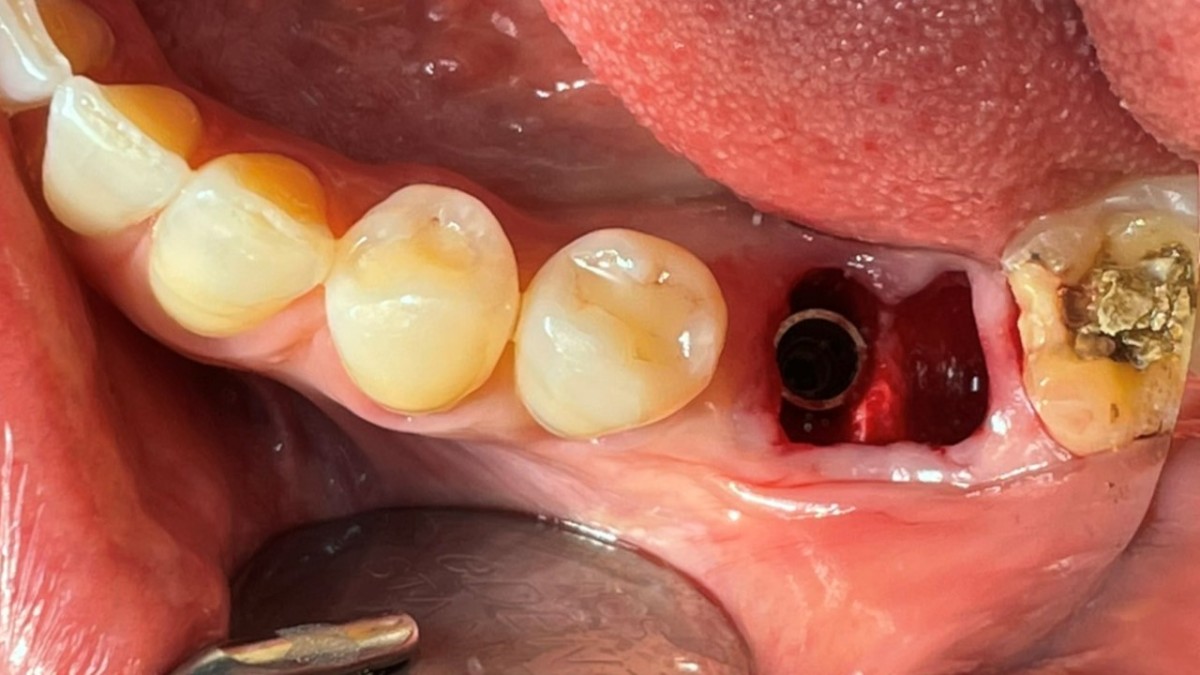

Immediate placement of an implant (Arum Dnetistry NB1, 5*8.5)

Immediate placement of an implant

A 51-year-old patient complained of an

old-crowned molar. The lower left molar had a gold crown, and the margin showed discoloration indicative of inner caries. Also, it had furcation-involved periodontitis

with an apical lesion.

Extraction and immediate placement of an implant.

▲Arum Dentistry NB1 fixture (5*8.5mm)